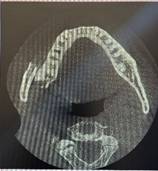

radiografía panorámica y TAC (tomografía axial computarizada), donde se evidencia la falta de continuidad del cuerpo y la rama de la mandíbula, lo que confirma el diagnóstico de fractura de ángulo mandibular, además de sensibilidad a los cambios térmicos como el frío y calor, por tanto provoca dolores y molestias al momento de abrir la boca, se identificó que esta patología fue provocada a causa de una exodoncia de tercer molar del sector inferior que comprometió la oclusión habitual del paciente y generó problemas de masticación y fonación, lo anterior  constituye el factor de riesgo primario. (Figura 1)

Figura 1. A. Radiografía panorámica que evidencia la solución de continuidad entre el cuerpo y la rama de la mandíbula del lado derecho. B y C, imágenes de TAC (tomografía axial computarizada).

Tomografía de haz cónico (TAC)

En estos tipos de lesión, la toma de una radiografía panorámica es de esencial importancia, así como la tomografía que es imprescindible durante las diferentes etapas del tratamiento, para poder culminar con éxito la resolución del traumatismo y la fractura mandibular ósea, por lo que es fundamental la obtención de una tomografía de alta calidad visual para dar un buen diagnóstico clínico, pues  brinda una visión 3D. (10)